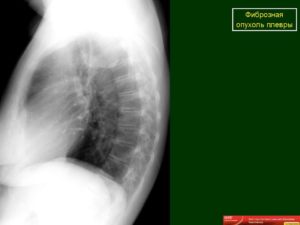

На рентгенограмме диффузное затемнение почти всей правой половины грудной клетки (рис. 1), за исключением небольшого участка верхней доли.

Рисунок 1 — Рентгенограмма грудной клетки больной Ц. в прямой проекции. Диффузное затемнение почти всей правой половины клетки.

Правый купол диафрагмы не дифференцируется. Верхняя граница затемнения представлена довольна четкой вогнутой линией. С внутренней стороны дополнительная тень сливается с тенью средостения.